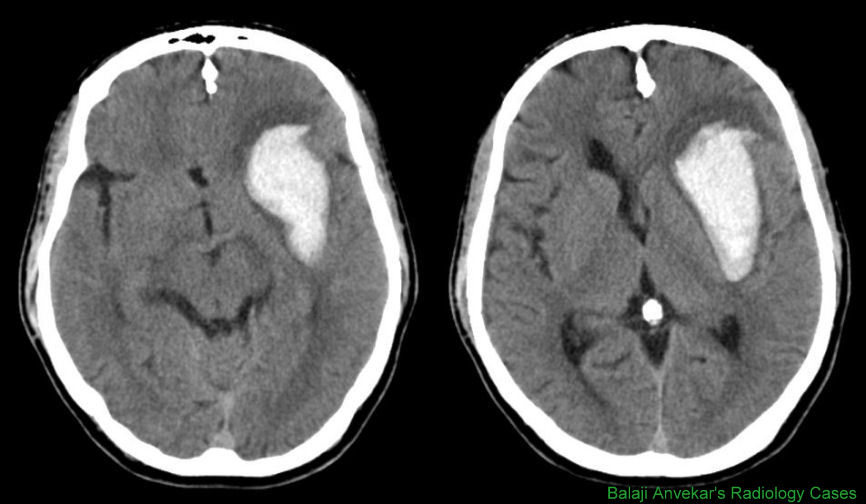

Intracranial Bleeds - Lieberman's ERadiology

Intracranial Bleeds Michael McWilliams, Harvard Medical School blood > brain due to globin protein in hemoglobin (Hct in hyperacute bleed is very high). - Therefore obtain NON-CONTRAST CT - attenuation increases 1. st . ... Access This Document